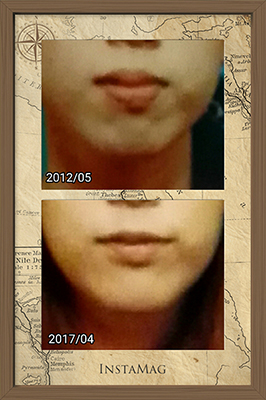

余談ですが最近、免許証の更新をしました。前回更新したのが5年前です。写真を比べると口元が全然違うのが分かります。

せっかくなのでその写真も一緒にアップします。